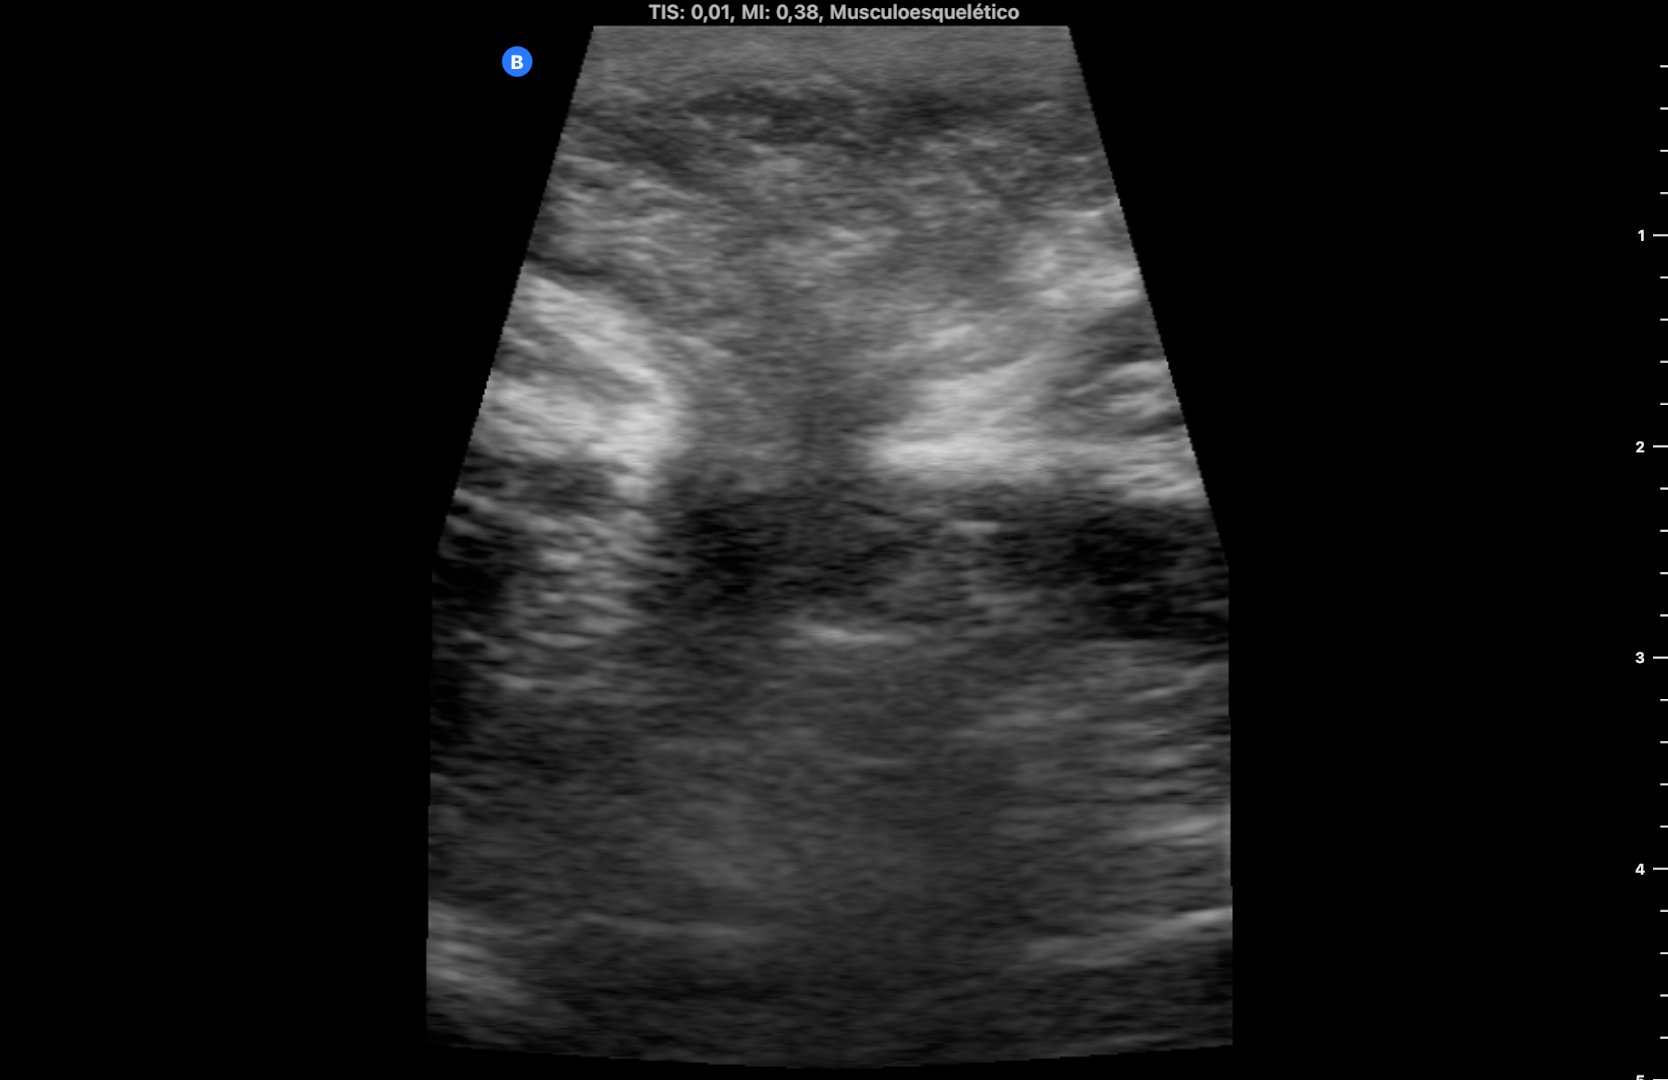

Se utiliza en la misma consulta una sonda portátil con preset de partes blandas, observando una imagen heterogénea redondeada, rodeada de líquido anecogénico a nivel subcutáneo que rompe la línea alba (imagen 1). Durante la exploración se comprime con la sonda en el lugar de la imagen consiguiendo la reducción de la misma y desapareciendo el dolor. La ecografía muestra entonces la discontinuidad de la línea alba con una pequeña protrusión de grasa (imagen 2) (se dispone de vídeos).

La ecografía en el ámbito de la Atención Primaria permite el diagnóstico (y a veces el tratamiento) en determinadas situaciones clínicas. Aunque el diagnóstico de hernia umbilical es clínico, la ecografía permite detectar los signos de sufrimiento (líquido periherniario) que indican la necesidad de reducción inmediata, y si no se consigue, derivación urgente al hospital.